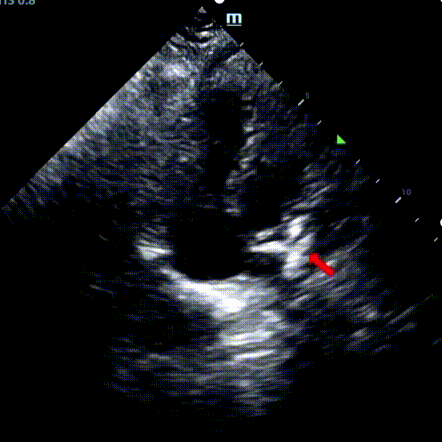

A 9-year-old male with secundum ASD (7.5–7.9 mm) was treated using a MemoSorb BDASD-I 12 mm occluder and 12F delivery system. No complications or comorbidities were noted pre-procedure.

Serial echocardiographic follow-ups showed stable device position and favorable cardiac remodeling. Gradual degradation confirmed the occluder's long-term safety and efficacy.